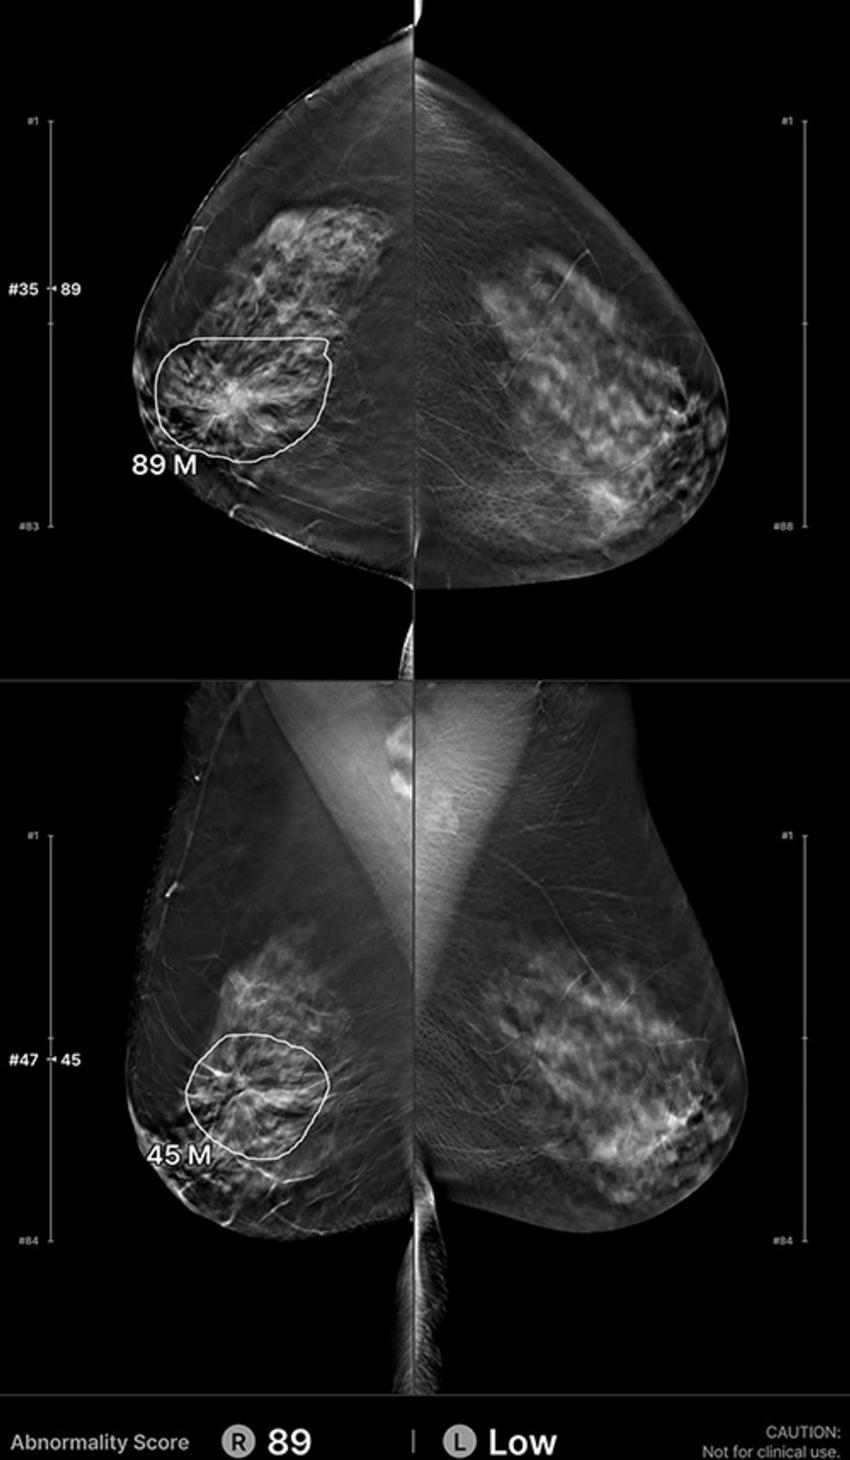

Figure 4. Example of a false-positive artificial intelligence (AI) classification. A 58-year-old woman presented for a screening digital breast tomosynthesis examination; its findings were interpreted as negative. Eight months later, the patient presented with a palpable area of concern in the left breast and was subsequently diagnosed with grade 2 invasive ductal carcinoma. At retrospective evaluation of the initial screening mammogram, the AI algorithm marked a lesion (white outline) in the contralateral (right) breast, with scores of 89 on the craniocaudal view and 45 on the mediolateral oblique view. This area of architectural distortion marked by the AI algorithm represents stable postsurgical changes. Of note, the AI vendor recommends caution with postsurgical cases.